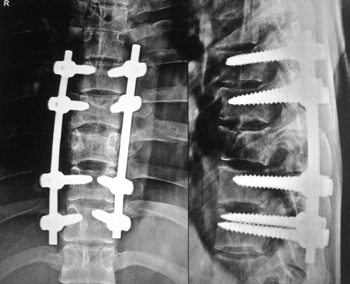

Only percutaneous pedicle fixation with G bone vertebroplasty for unstable burst fracture.